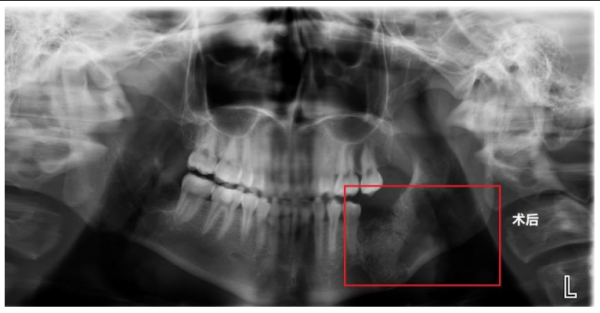

术后X片显示,被囊肿侵蚀的颌骨缺损区已成功植入人工骨材料

在经过充分的术前准备后,贺祖武带领团队利用超声骨刀精准去骨,最大程度减少患者的术区创伤,保留足够的颌骨骨量,尽量避免下颌骨出现病理性骨折。术中,还同期应用浓缩生长因子(CGF)凝胶混合骨填充材料,植入术区的创口,促进骨组织再生及愈合,确保术后功能与美观兼顾,极大限度减少对患者生活质量的影响。手术历时1小时顺利完成,患者术后恢复良好,次日即可进食流质饮食。术后X片显示,其被囊肿侵蚀的颌骨缺损区已成功植入人工骨材料,为后续种植牙打下基础。